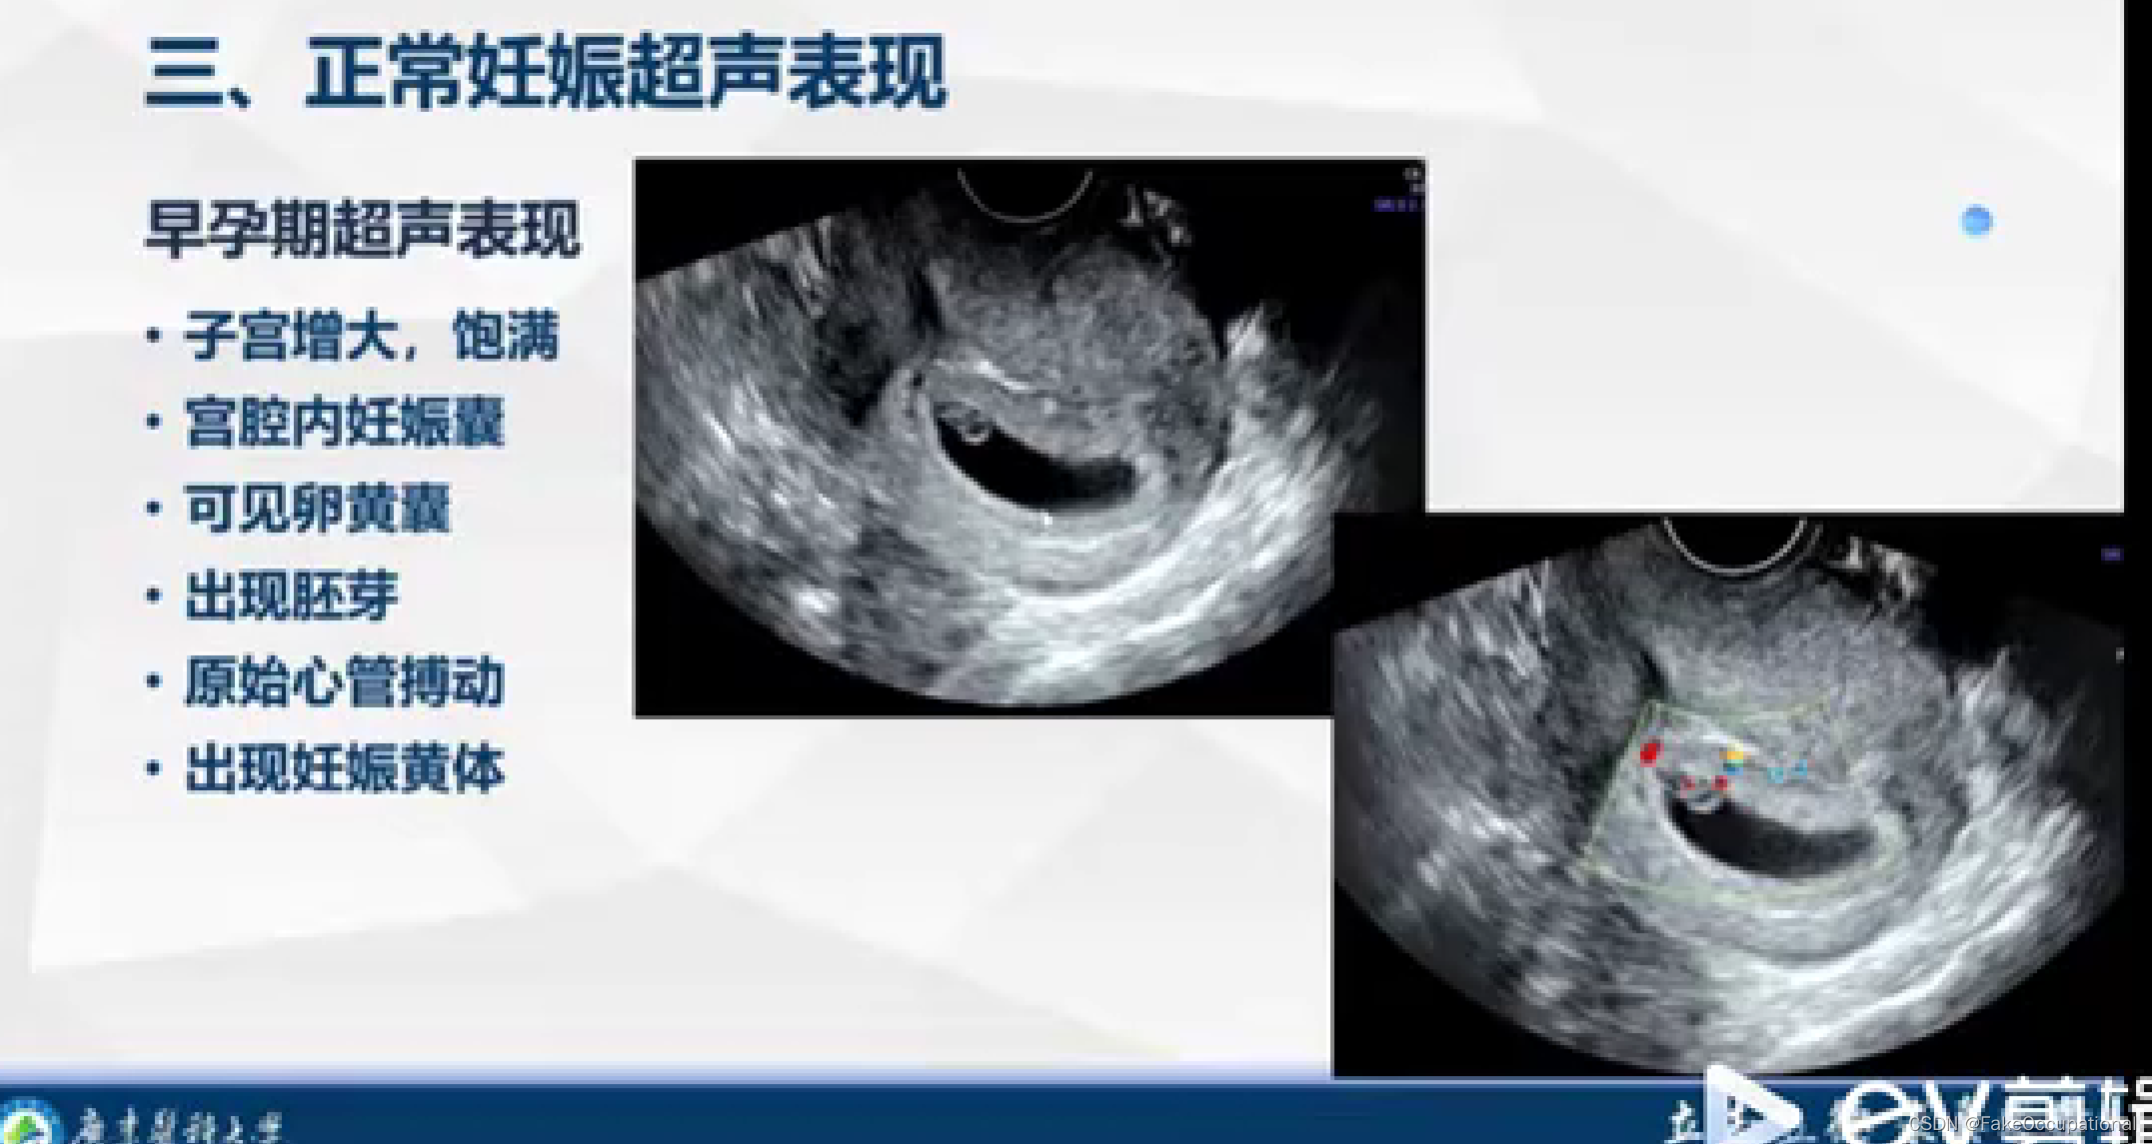

产科超声

产科常见病超声表现